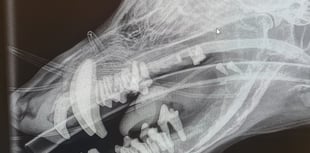

Barry's 'Rubber Jaw' Treated at South Moor